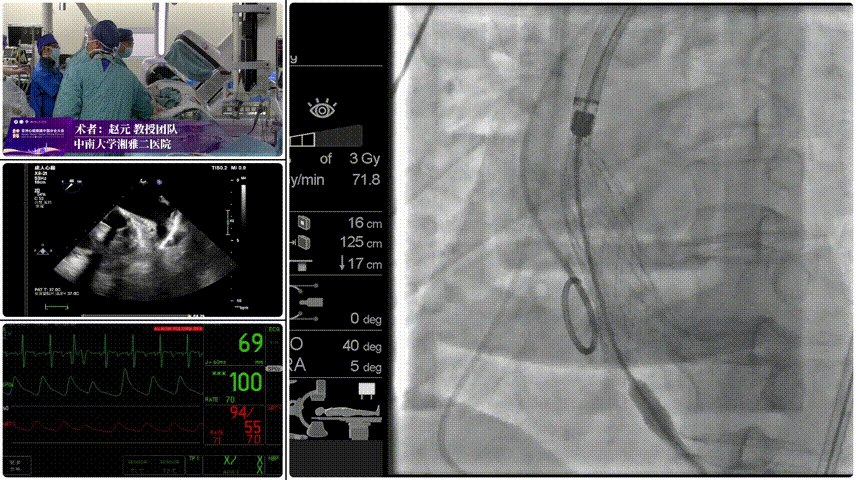

Step 2.定位释放:初始高定位,使瓣膜自然下滑至理想位置。

Step 3.工作位评估:位置合适,深放以避免瓣膜开合区过度受挤压。

瓣膜输送系统的柔顺过弓设计成为本次手术的核心亮点。系统采用短瓣架设计、易过弓专利技术与超滑亲水涂层,配合内联鞘小尺寸设计(等效 14F),完美适配细入路血管。手术中,介入团队在 DSA 引导下缓慢推进输送系统,凭借器械优异的柔顺性,在锐角弓解剖结构中实现一次性柔顺过弓,全程未出现器械卡顿、血管牵拉或钙化斑块剐蹭现象,过弓过程仅耗时1分钟,大幅降低了卒中与夹层风险。此外,内联鞘小尺寸设计有效减轻了对股动脉血管壁的机械损伤,术后血管闭合良好,未出现出血、血肿等并发症。

手术过程与术后转归